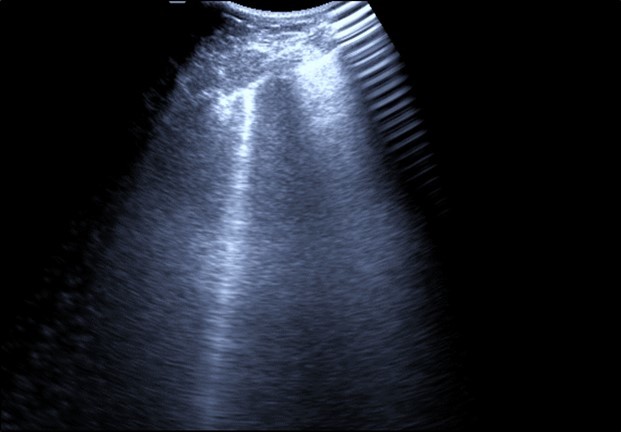

Bed side chest ultrasound may reveal positive findings as multiple Kerley’s B lines (>3 per intercostal space), pleural wall thickening (Figure 1), patchy areas of pulmonary consolidations especially in subpleural location (Figure 2, Figure 3) and obstructive lung collapse.

Figure 1.Real time chest ultrasound showing Kerley’s B lines in patient with covid -19.